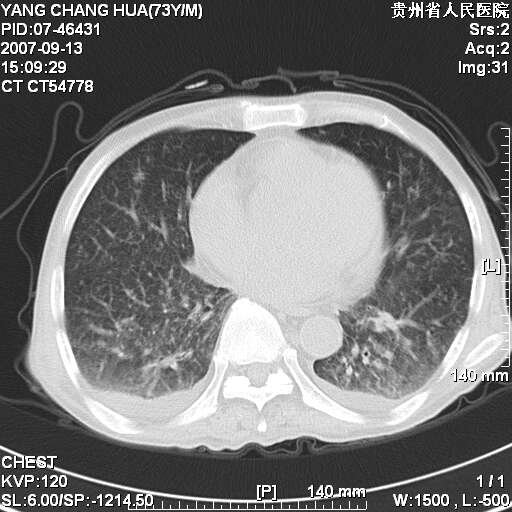

图像没有传全。肺部为感染性病灶;肺囊肿;双侧胸腔积液;肝脾肿大;腹水。

双肺部为感染性病灶.双侧胸腔积液;肝脾肿大;腹水.

双肺部为感染性病灶.双侧胸腔积液;肝脾肿大;脾脏密度不均,不除外脾侵润?腹水.

双肺点片状影,以双上肺改变明显.双侧胸腔积液.为感染性病灶,但不除外结核.

双上肺继发型肺结核。

双肺散在斑片状及多发小结节状阴影,边缘模糊,双上肺野明显,双侧胸膜腔少量积液,纵隔及肺门区未见明显肿大淋巴结,肝脾肿大,脾内见多发低密度区,结合临床考虑恶性淋巴瘤(肺内表现为肺炎肺泡型),单看影像表现,肺结核不能排除。建议结合实验室检查或表浅淋巴结活检。